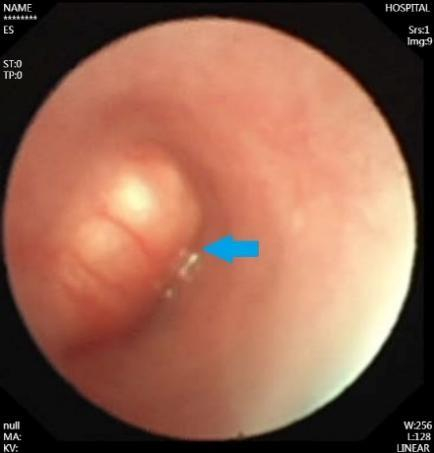

术前纤支镜检查,箭头处为肿物

入院后,李乐主任团队为小琪完善了胸部CT和纤支镜检查,发现肿瘤位于气管隆突附近,几乎将左主支气管完全堵住,如果肿瘤再侵犯气管隆突或者右主支气管,就会有窒息的危险。针对小琪的病情,胸外科迅速组织麻醉科、呼吸科、PICU、影像科等多学科会诊和讨论,决定尽快手术治疗,切除气管肿瘤并重建气管。